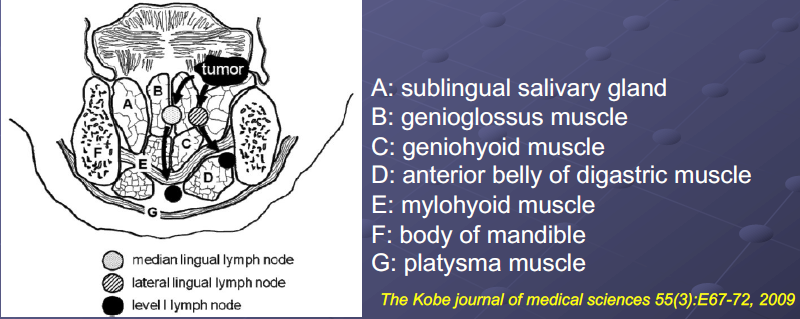

Lingual Lymphatic nodes

病灶

舌頭

Structure

- Terminal sulcus(terminalis)分前後